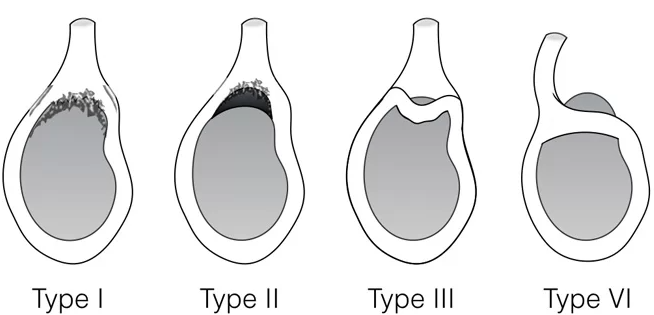

▶ SLAP lesion 4type

- 제1형 : 관절와순은 관절와에 부착되어 있으나 마모 및 변성이 있는경우(이두장건 부착부는 분리되지 않은 상태)

- 제2형(가장 흔한 유형) : 관절와순 및 이두장건의 박리가 있는경우(이두장건 부착부위가 파열되어 일부 분리)

- 제3형 : 양동이 손잡이 파열로서, 상부관절와순이 파열되어 관절안으로 전위되었으나 이두장건 부착부위는 손상이 없는경우

- 제4형 : 상부관절와순의 파열이 이두장건까지 연장되어 있으며 관절안으로 전위되어있는경우로서 드문 유형입니다.